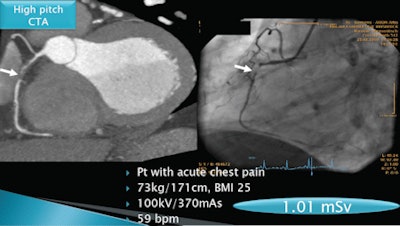

Austrian radiologists have found a way to cut the radiation dose of coronary CT angiography (CCTA) studies to as low as 1 mSv by using a high-pitch scanning protocol on a 128-slice scanner for patients with low heart rates.

Traditional retrospectively gated 64-slice coronary CTA is associated with relatively high radiation doses of approximately 12 mSv, but an emerging high-pitch CT angiography technique, performed on a 128-detector-row dual-source scanner, can reduce dose significantly, said Tobias DeZordo, MD, from the Medical University of Innsbruck. DeZordo presented his group's research on the subject at the 2010 RSNA meeting in Chicago.

DeZordo, along with lead researcher Gudrun Feuchtner, MD, and colleagues, acquired all images on a 128-detector-row dual-source CT scanner (Somatom Flash, Siemens Healthcare, Erlangen, Germany). The high-pitch Flash protocol uses a pitch setting of 3.4, prospective ECG synchronization, and a short scan time of only 0.3 seconds, he said.

- High-pitch Flash sequence for patients with heart rates < 60 bpm

In four patients (0.5%), high-pitch CTA had nondiagnostic image quality for at least one coronary artery (right circumflex artery, n = 4; circumflex, n = 1). In each of these patients, heart rates increased during the CT scan to higher than the 60 bpm threshold for optimal Flash scanning (captured heart beats: 60, 61, 61, and 63 bpm). When this occurred, a sequential (n = 3) or spiral (n = 1) exam was appended to ensure diagnostic image quality, DeZordo said. The total radiation exposure in these patients was a mean 3.9 mSv (representing the additional sequence) and 13.5 mSv (representing the additional spiral acquisition).

| Coronary artery stenosis is detected by coronary CTA (left) and conventional angiography (right) in a patient with acute chest pain. All images courtesy of Gudrun Feuchtner, MD. |

"High-pitch Flash mode scanning is reliable for coronary CTA if the heart rate is lower than 60 bpm, and high-pitch scanning allows for low radiation dose as well as [lower] contrast agent volume," DeZordo said. "High-pitch spiral mode can be integrated in clinical cardiac CT practice using our proposed triage, and permits a tenfold radiation dose savings and contrast volume savings."